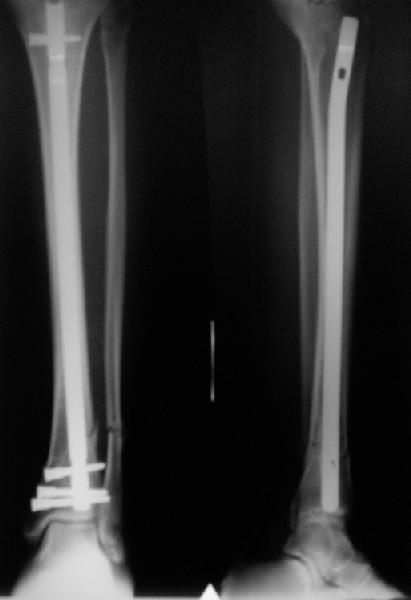

A typical case is attached, also an image with intra-op reduction obtained by a small wire distractor, in the moment of insertion a Poller wire in AP direction. Fixation by a SIGN nail. Despite the fibula was not fixed healing was obtained with the unchanged alignment.

I am just trying to illustrate that prevention of 1)tibial valgus and 2)loss of reduction can be provided without fibular plating. Small changes of conventional nailing techniques allow to maintain reduction of the tibia reliably without adjunctive fibular stabilization.

In delayed cases acute length restoration performed only in the tibia may leave the fibula shortened thus change the mortise. So it is reasonable to restore length of both bones simultaneously by distractor and fix the fibula not with open reduction and plating but just by a single perQ screw. Example attached.